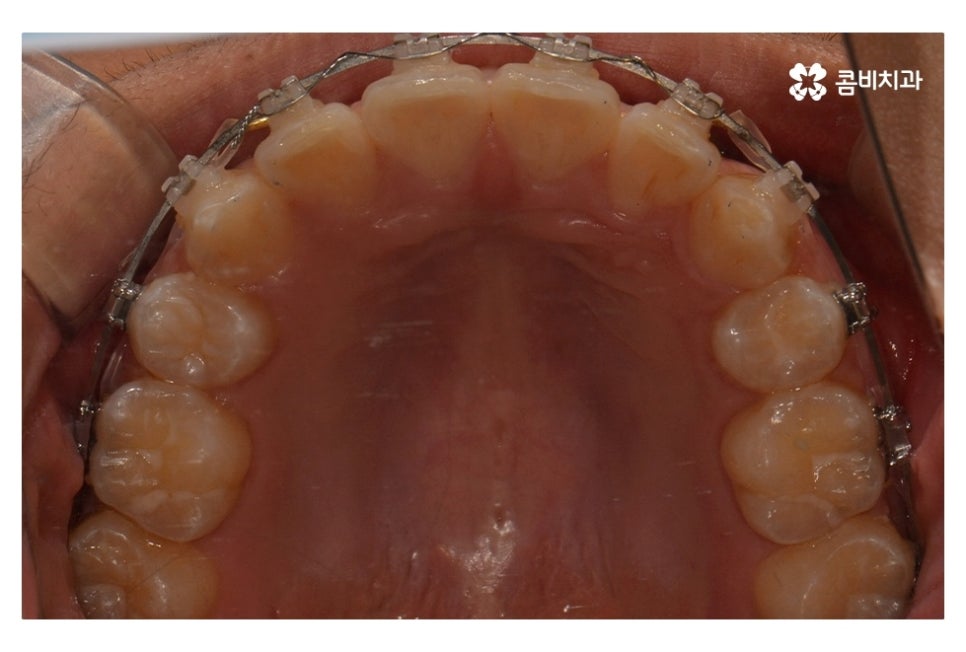

위 사진에서 보시면 시간이 지나면서 발치를 했던 치아의

공간이 사라지고 교정을 통해서 치열이 가지런해진 것을 확인할 수 있는데요.

중학생치아교정에 있어서 중요한 사항이 단지 치열만이

가지런해 보이는 것이 아닌 얼굴과의 조화와 교합이라 할 수 있어요.

조화를 충분히 생각해야 하며 치료 후 결과가 잘 유지되고

건강하게 치아와 잇몸이 자리 잡을 수 있도록

유지관리의 중요성도 크다고 볼 수 있어요.